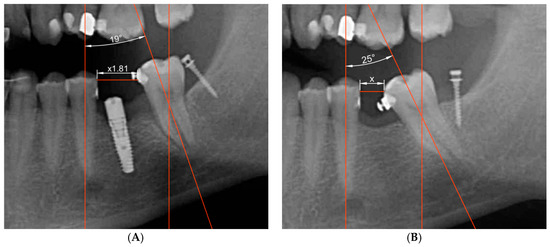

Evaluation of the efficacy of miniscrew treatment was performed using orthopantomographs taken before and after treatment. The orthopantomographs were taken at the Department of Radiology attached to the University of Valencia Dental Clinic by the department staff. Measurements were always taken by the same operator to avoid any discrepancies derived from different interpretations of the radiographs. To avoid possible radiographic distortion, the length (in millimeters) of the miniscrew determined by the manufacturer was used as a reference value; all radiographs were scaled according to this length. The amount of prosthetic space obtained was determined by calculating the difference between baseline measurements taken at the moment when the miniscrew was placed (T0) and measurements taken after implant insertion (T1). Measurements were taken using AutoCAD® software (Autodesk Inc., San Rafael, CA, USA). To evaluate the prosthetic space gained as a result of treatment, the distance from the most distal point of the second premolar crown to the most mesial point of the second molar crown was measured at both evaluation times (T0 and T1, post- and pre-treatment) comparing the measurements obtained (Figure 3A,B).

Figure 3.

(A) Illustration of pre-treatment angulation and distance measurements taken from radiographs. (B) Illustration of post-treatment angulation and distance measurements taken from radiographs.

To determine the prosthetic space created, the measurement schema described below was followed, in which dashed lines represent angulation measurements and continuous lines represent distance.

When the radiographs were scaled, measurements were taken as follows:

Angles measured before and after treatment were compared to evaluate changes in second molar angulation by tracing the vertical axes of the second premolar and the second molar on the radiographs. A line was drawn parallel to the second premolar axis passing through the second molar furcation. Finally, the angulations between the second molar axis and the second premolar axis were compared in pre-treatment and post-treatment radiographs.